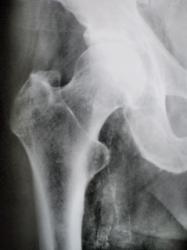

Иллюстрация 2, 3. Медиальнее шейки и проксимального мета-диафиза бедренной кости, на фоне мягких тканей определяются тени двух венозных сосудов, с выраженным отложением солей извести в их стенках.